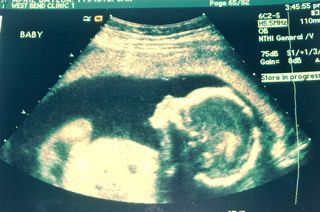

Ultrasound in medicine can visualise muscle and soft tissue, making them useful for scanning the organs, and is commonly used during pregnancy. Ultrasound is a safe, non-invasive method of looking inside the human body.

Ultrasound image of a unborn baby